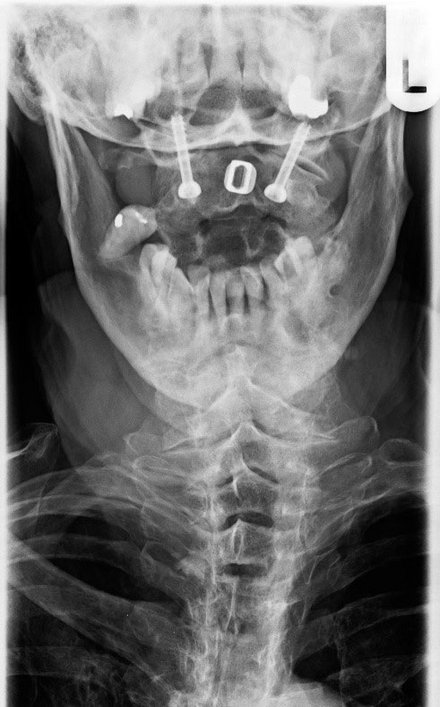

Bestimmte Erkrankungen aus dem rheumatischen Formenkreis können zu entzündlichen Veränderungen an den ersten beiden Halswirbeln führen. Hierbei kann es zu einer lebensbedrohlichen Instabilität kommen, die zwingend operativ behandelt werden muss. In unserer Klinik findet eine speziell entwickelte und zu etablierten Verfahren modifizierte OP-Technik Anwendung, die aus hiesiger Sicht die möglichen und schwerwiegenden Komplikationen vergleichbarer OP-Techniken verringert (z. B. Verletzungen der Schlagadern). Hierbei wird von vorne eine Verschraubung der Gelenke HWK-1 und HWK-2 vorgenommen, um dann nach Umlagerung in die sogenannte sitzende Körperposition einen aus dem Beckenkamm gewonnenen Knochenspan zwischen den Dornfortsätzen des 1. und 2. Halswirbels einzufalzen und über eine Cerclagetechnik weiter zu fixieren. Diese Technik hat sich nicht nur in der Rheumachirurgie bewährt, sondern kommt auch bei der Behandlung von schweren Verschleißveränderungen oder auch Missbildungen der oberen Halswirbelsäule zur Anwendung.